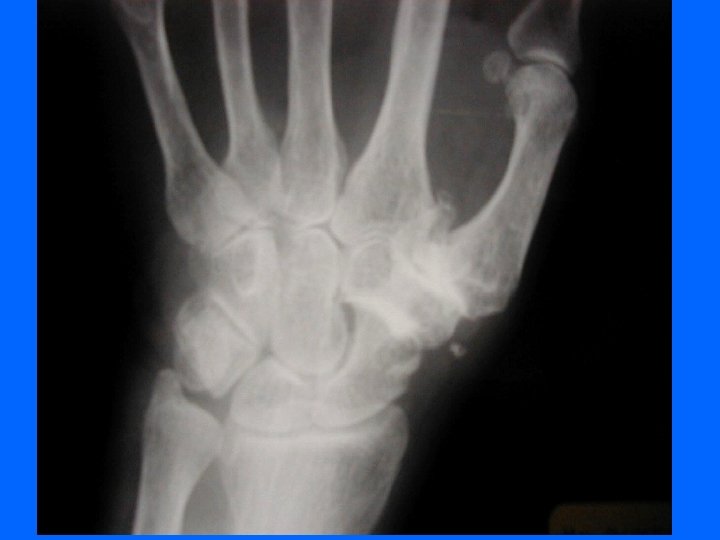

Comment faire le diagnostic ? • Le diagnostic est clinique : déformations typiques • Les radiographies : mains de face – pincement de l’interligne – une ostéophytose latérale en berge, très exubérante responsable des nodosités – géodes sous-chondrales